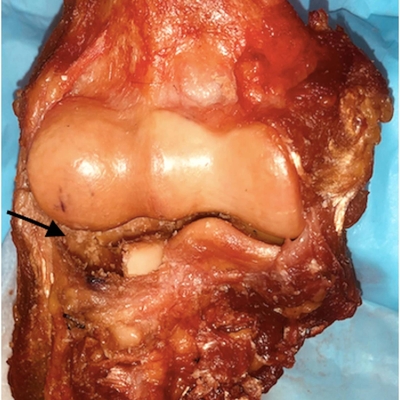

Click on an image below to view more info.